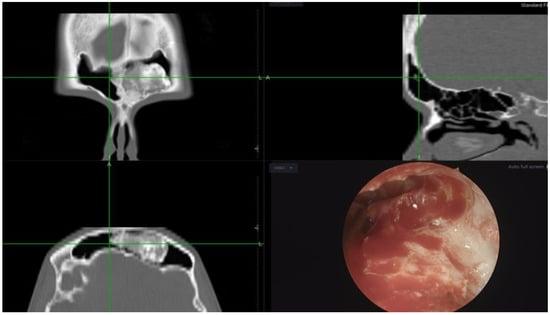

In approximately two-thirds of the patients we used the lateral-to-medial (inside-out) approach, while in oncological cases involving benign and malignant sinonasal tumors we used the medial-to-lateral approach. Mucosal flaps and free grafts were utilized in 36% of cases, with the exception of malignant cases where they were never employed. Specifically, free grafts were utilized in 30.8% of cases with flaps/grafts, laterally based flaps in 61.5%, and middle turbinate septal flaps in 7.7% (Scheme 2, Figure 1).

Figure 1. (A) Intraoperative perspective depicting the unified frontal sinuses subsequent to a Draf III procedure, prior to flap placement. Note the extensive bone exposure following the drill-out; (B) the laterally based flap (left side), mobilized for coverage of the exposed bone (asterisk denotes base of the flap); (C) conclusive view displaying the flap in situ (asterisks denote flap placement, green indicates neo-ostium, purple represents septal window); and (D) a 0.25 mm silastic sheet utilized to secure the flap (asterisks) postoperatively for 4–6 weeks.